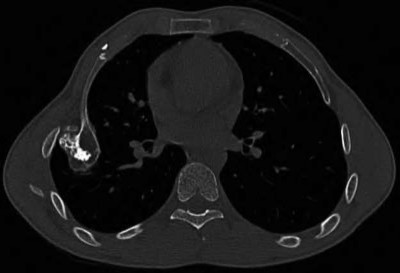

A 20-year-old park ranger trips and falls onto his right wrist with the wrist in extension and pronation. The local urgent care orders both radiographs and a CT, which you review and determine to be normal. The patient complains of ulnar-sided wrist pain. On exam, his tenderness is localized to the fovea. Ulnar deviation also causes him pain. There is no snapping sensation with wrist supination, flexion, and ulnar deviation. He otherwise has 5/5 strength to his first dorsal interosseous muscle with 4mm static two-point discrimination on the ulnar side of the 4th digit. Which of the following injuries is most likely responsible for his symptoms and exam?